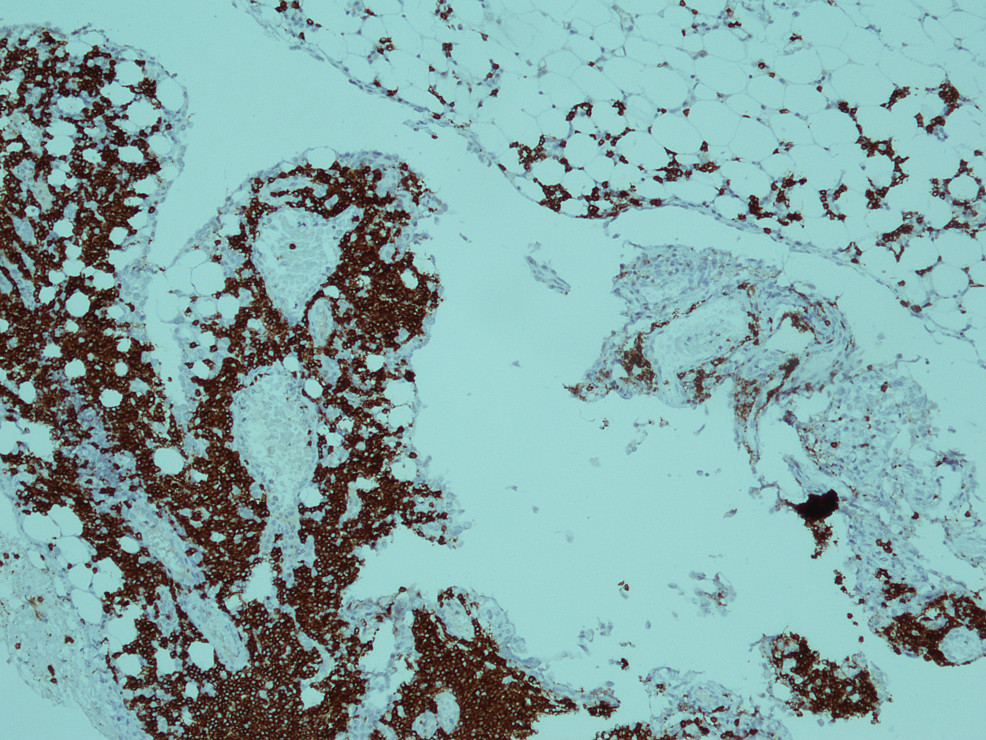

Ultimately CT abdomen showed gross ascites with omental thickening and nodularity (Figures 1-2). A laproscopic omental biopsy was performed. Grossly omentum and gut loops appeared normal. However, omental biopsy showed atypical lymphoid infiltrate (Figure 3). Immunohistochemistry showed lymphocytes positive for CD20 and Tdt while CD10 negative (Figures 4-5). In correspondence with these results precursor B-cell lymphoblastic lymphoma was diagnosed. After discussing the biopsy report with the child’s parents CHOP therapy has been initiated.